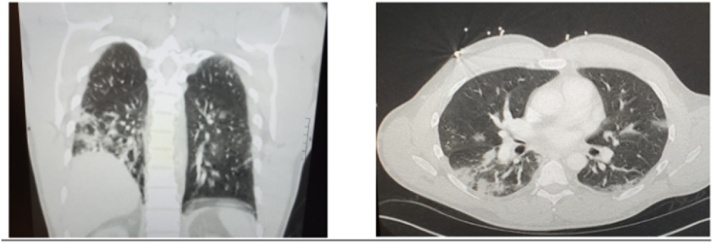

A 41-year-old male with a past medical history of well controlled HIV, maintained on dolutegravir-lamivudine with last CD4 count of 604 cells/cu mm and an undetectable viral load two months prior to presentation and recurrent HSV on chronic suppressive therapy presented with abdominal pain, intractable vomiting, and confusion. He became ill six days prior to presentation when the patient started experiencing a dry cough and intermittent fever relieved by antipyretics. On day of presentation, he was only oriented to self. Remainder of symptoms and their development are outlined in Fig. 1. His epidemiologic risk factors for COVID-19 included indirect exposure to a COVID-19 positive patient. Full lab work on day of presentation including COVID-19 testing was performed. Results on day 1 (Table 1) were pertinent for leukopenia. EKG showed sinus tachycardia with first degree AV block and a QTc interval of 424 ms. No respiratory distress was noted. CT chest revealed diffuse patchy nodular ground glass infiltrates (Fig. 2). The remainder of imaging studies including CT head were unremarkable.

Fig. 2.

CT scan of the chest with coronal (left) and cross sectional (right) views showing diffuse patchy peripheral ground glass infiltrates most consolidative within the right lower lobe.